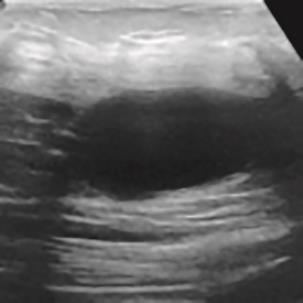

乳腺癌是全球女性最常见的恶性肿瘤之一,准确的病变分割对于乳腺癌的早期诊断与治疗具有重要意义。然而,由于病变形态的多样性以及超声成像机制的复杂性,现有基于深度学习的乳腺超声图像病变分割方法在分割准确性方面仍面临巨大挑战。为进一步提升乳腺超声图像中病变区域的分割精度,该文基于经典U-Net架构,提出了一种新型乳腺超声图像病变分割网络(CWSASKM-BBAM-Net)。首先,在网络中引入逐通道空间自适应选择核卷积模块(CWSASKM),根据不同通道的语义特征为每个空间位置自适应选择感受野大小,以增强多尺度信息的建模能力;然后,引入双向边界感知机制(BBAM),通过融合正向与反向注意力,对目标显著区域及其边界进行协同建模,同时逐步提升对非显著区域与病变区域的区分能力,以进一步强化边界信息的表达;最后,在3组公开乳腺超声图像数据集(BUSI、UDIAT和STU)上开展分割实验。结果表明:该方法在数据集BUSI上的杰卡德指数、精确率、召回率和Dice相似系数分别为71.97%、82.85%、81.40%和80.44%,较次优方法分别提升1.69、1.05、1.28和1.84个百分点;在数据集UDIAT上,这4项指标分别达到78.14%、88.31%、86.73%和86.10%,较次优方法分别提升了2.75、2.04、0.56和2.01个百分点;在外部数据集STU上,该方法也取得了优于其他方法的整体表现。实验结果表明,CWSASKM-BBAM-Net在乳腺超声图像分割任务中展现出更优的整体性能。